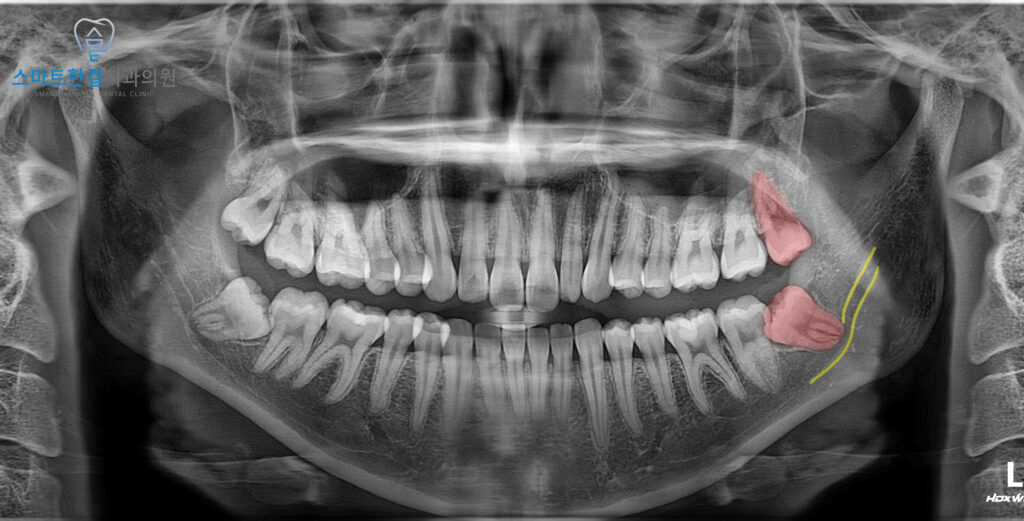

파노라마 사진에서는 왼쪽 아래 사랑니가

잇몸 안에 묻혀 있으면서

앞 치아 쪽으로 비스듬히

누워 있는 모습이 확인되었어요.

또한 육안으로 살펴보았을 때

잇몸이 약간 부어 있는 상태였어요.

잇몸 부기의 원인이 사랑니일 가능성이 높고,

비스듬히 누운 사랑니가 앞 치아에 영향을

미칠 우려가 커 왼쪽 아래 사랑니를

발치하는 동시에 위쪽 사랑니도

함께 발치하기로 결정하였답니다.

또한, 사랑니의 뿌리와 신경관이

파노라마 사진에서 중첩되어 확인되어,

발치 전 3D CT 촬영을 통해 정밀하게 분석한 후

안정적으로 발치를 진행했어요.